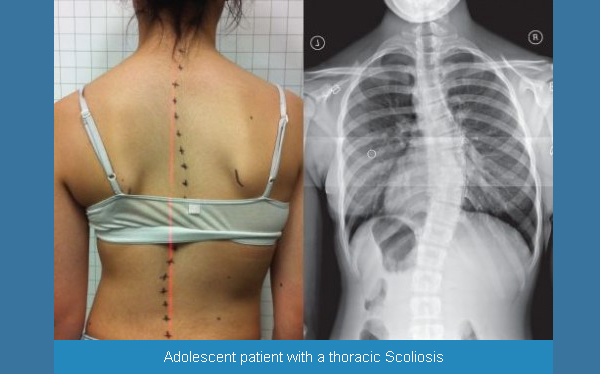

Искривление позвоночника: причины и последствия на снимках